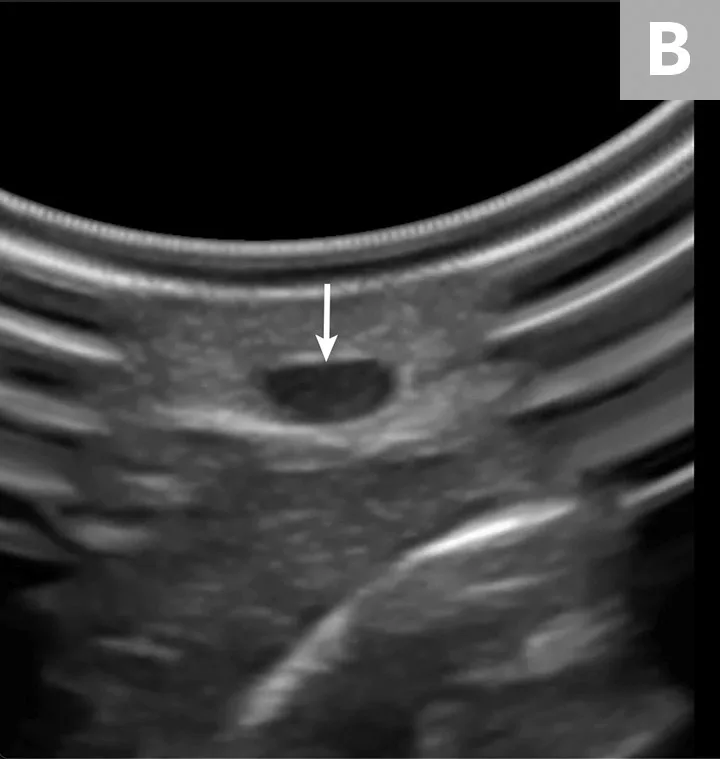

Place the probe on the skin at a 90-degree angle to the vessel (A). Use probe manipulations (eg, sweeping, sliding, rocking, fanning) to identify and situate the vessel (B, arrow) in the horizontal center of the ultrasound display.

Gloved hands holding ultrasound probe over limb of pet and ultrasound image with arrow pointing to blood vessel.